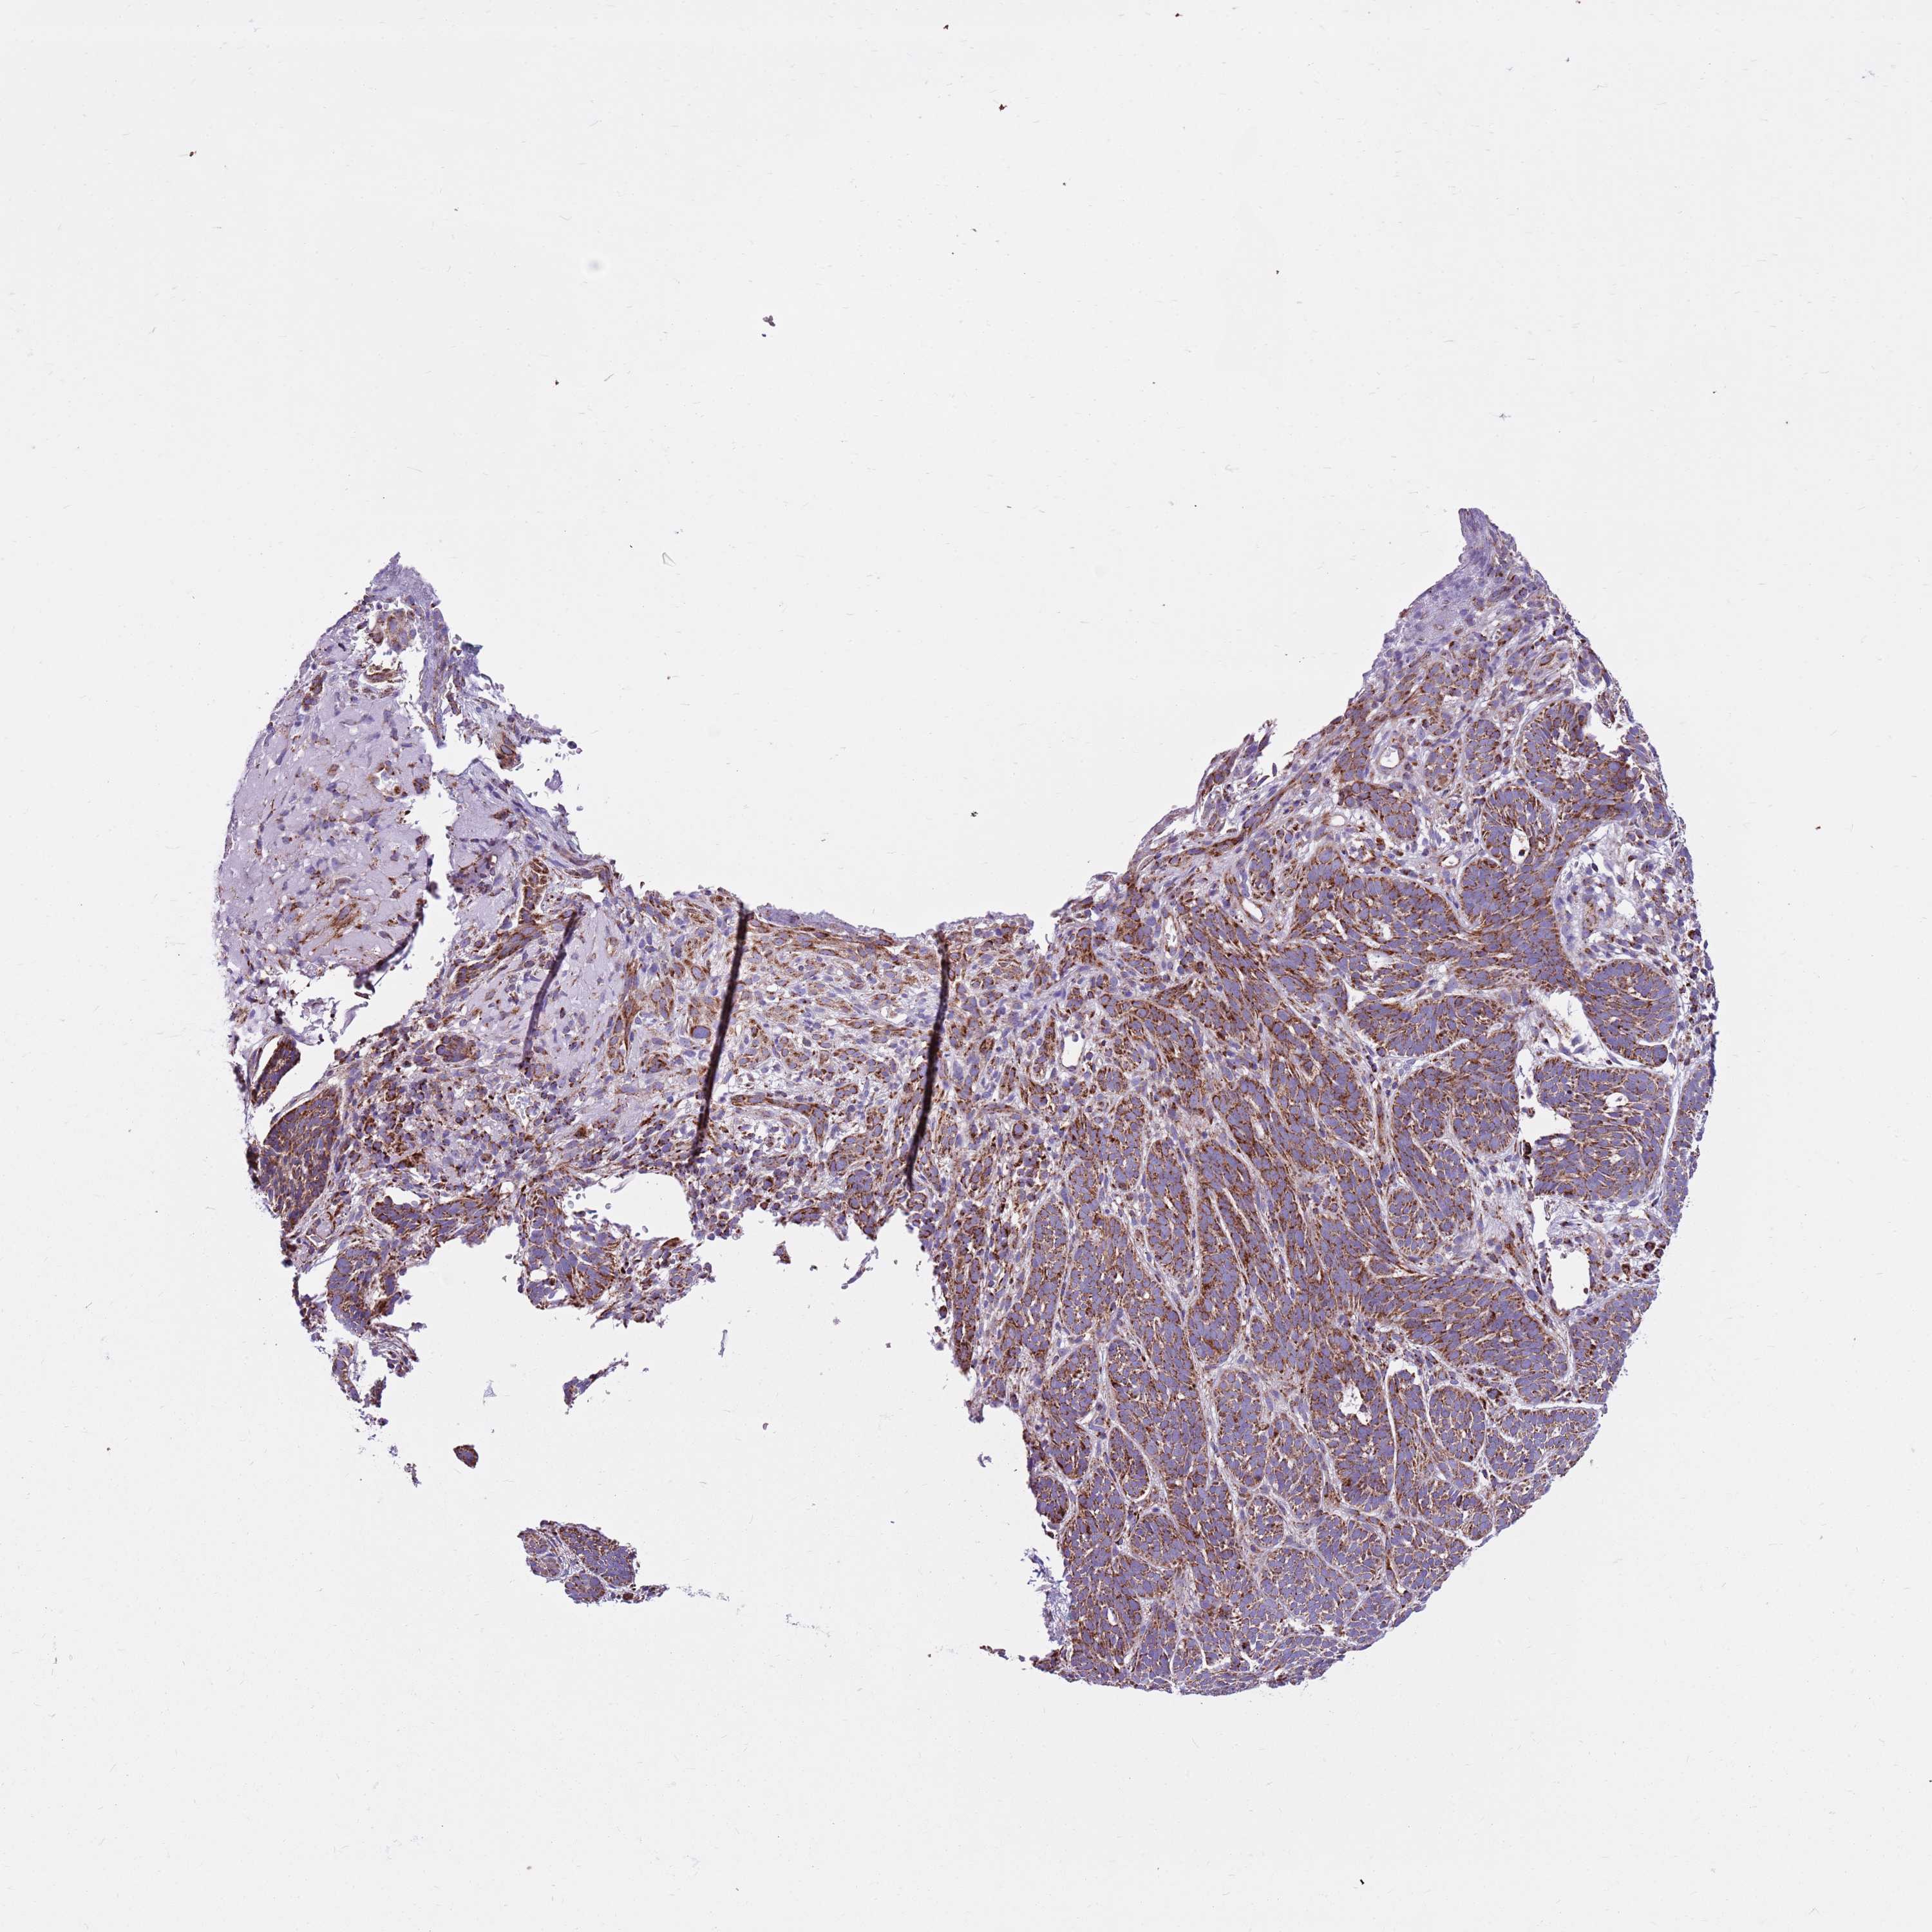

SKIN CANCER - Protein expressioni

A mouse-over function shows sample information and annotation data. Click on an image to view it in a full screen mode. Samples can be filtered based on level of antibody staining by selecting one or several of the following categories: high, medium, low and not detected. The assay and annotation is described here.

Antibody stainingi

Antibody staining in the annotated cell types in the current human tissue is reported as not detected, low, medium, or high, based on conventional immunohistochemistry profiling in selected tissues. This score is based on the combination of the staining intensity and fraction of stained cells.

Each image is clickable and will lead to virtual microscopy that enables deeper exploration of all samples and also displays staining intensity scores, fraction scores and subcellular localization as well as patient and tissue information for each sample.

Antibody HPA041062

Antibody HPA045473

Basal cell carcinoma

Squamous cell carcinoma, NOS

Squamous cell carcinoma, metastatic, NOS